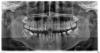

Александр Феодоров Опубликовано 7 августа, 2013 Поделиться Опубликовано 7 августа, 2013 Добрый день, дорогие врачи со всего мира! Меня зовут, Александр Феодоров!Я хочу кратко, описать свою жизненную ситуацию с полостью рта, и верю в вашу помощь: Уже очень давно, когда мне было 13-15 лет (сейчас 24) мне говорили врачи в школе, что у меня неправильный прикус зубов, но не объяснили толком, что это означает. Также когда, меня призывали в Армию, тоже про это говорили, но опять же не рассказали, к чему это может привести в итоге - именно по этому я не уделил, должное внимание это вопросу!А спустя, как 2-3 месяца, я начал замечать, что у меня у пары нижних зубов|3-4-5 слева : 4 справа| а также у верхнего |5 справа| начинают, уходить десна и становятся видны больше чем прежде зубы! Это мне насторожило, и я начал, посещать разных стоматологов в г.Казани, с целью узнать, что это и как сделать так, чтобы полость рта была здоровой. Прилагаю, снимок - для лучшего понимания, ситуации. Если нужны, будут еще снимки какие-то напишите, я обязательно сделаю! Они мне давали похожие рекомендации:(в разной последовательности - кто-то, говорил, что-то из этого а про другие не заикался) 1.Убрать тяжи снизу челюсти (чтобы десны не уходили)2.Удалить |4-ые зубы с верхней и нижней челюсти|3.Поставить брекеты4.Поставить иплонтанты зубов |на месте тех, которые удалили 4-ые| Я хочу для себя осознать, с вашей помощью, каковы истинные причины, того что происходит, и как сделать так, последовательно, чтобы прийти к здоровой полости рта?*Желательно, без удаления зубов и установки имплонтантов!Благодарю, жду ваших компетентных - профессиональных советов в этом направлении. С уважением, Александр Феодоров 1 Ссылка на комментарий